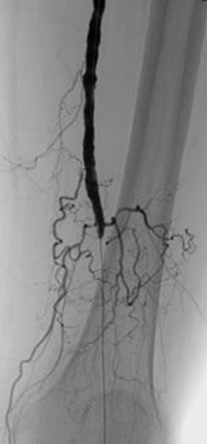

Oclusión de la arteria poplítea proximal.